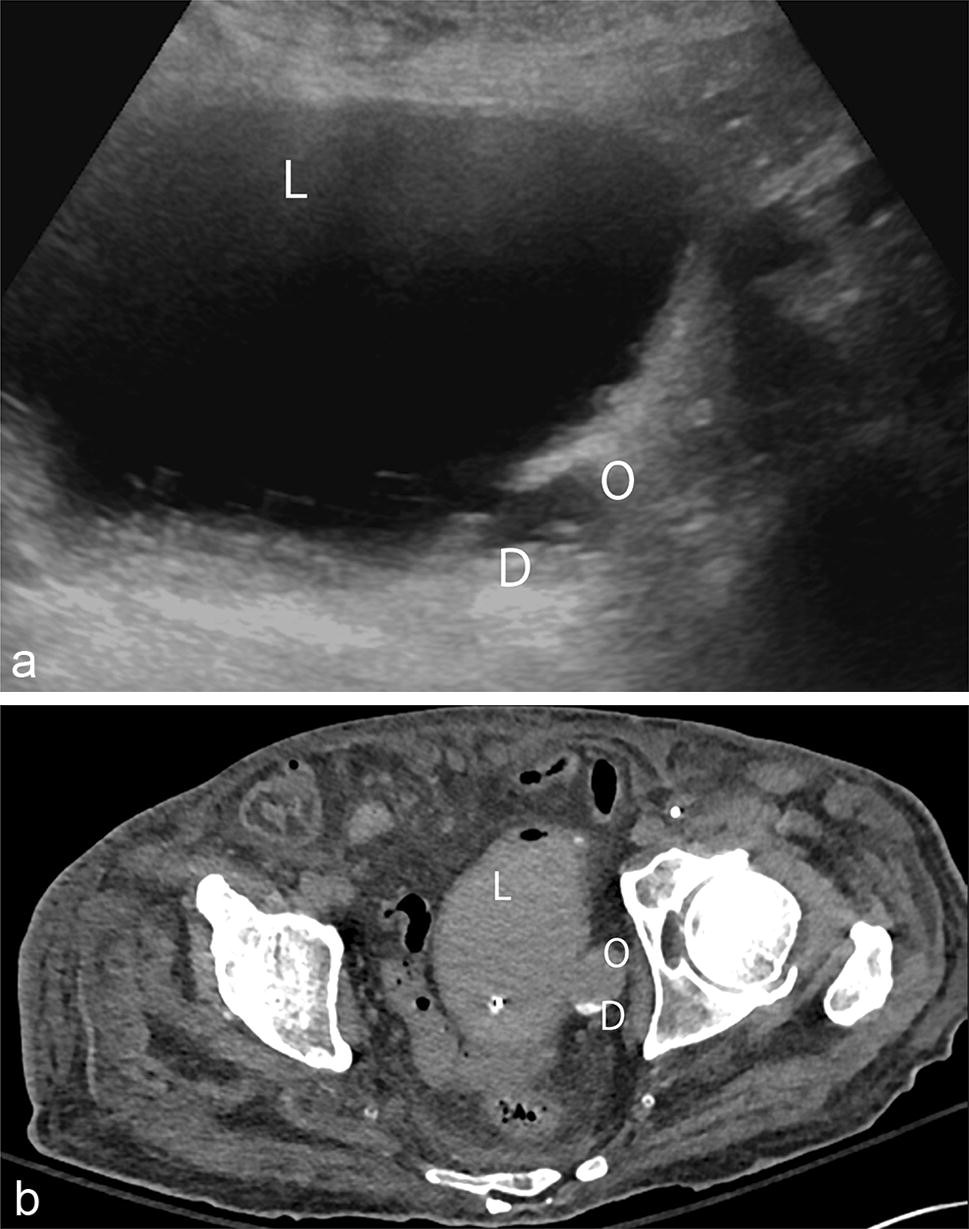

Bladder outlet obstruction can be uncomfortable and lead to severe problems in a man's body. Distention of the bladder due to the retention of urine may be caused by one of two mechanisms : Narrowing of the tube that carries urine out of the body from the bladder (urethra), due to scar tissue or certain birth defects.

Hi, when a patient gas symptoms of slow urunary flow, sense if incomplete evacuation of urine, with intermittent stream with straining to void urine, he is suspected if having bladder outlet obstruction which us fairly common in. Decreased flow of urine leads to swelling of the urinary tract, called hydronephrosis. It is often caused by enlarged prostate. Bladder outlet obstruction (boo) has very similar presenting symptoms to what we have seen with an underactive detrusor but, the causes are very different.